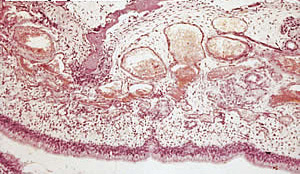

| Sección histológica de hocico de cerdo con Rinitis Atrófica: resorción ósea con hiperplasia de los osteoclastos y sustitución por tejido fibroso, congestión de los vasos capilares, edema y presencia de una infiltración de la submucosa por células mononucleares. |

Asistimos pues a una atrofia de las glándulas mucosas, una hiperplasia del epitelio, un aumento del volumen de los vasos sanguíneos y una acentuación de la osteolisis. La trama ósea, los tejidos osteogénicos y osteoclásticos son reemplazados por un mesénquima.

Microscópicamente hablando, la Rinitis Atrófica Progresiva puede ser vista como una combinación de una degradación precoz de la osteogénesis, de una ostelisis marcada y de un reemplazo del hueso por una estructura fibrosa.